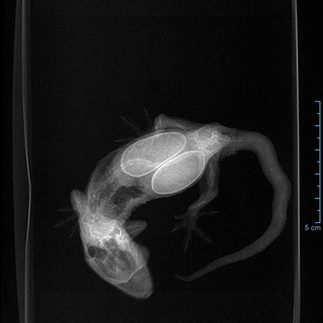

You can check out our gallery of family pets HERE. Including Geckos, Crabs, Frogs, Stick Insects and even our Axolotl, Antonio.